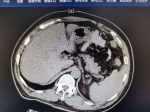

高處墜落傷致腹腔積血非手術(shù)治療和手術(shù)治療的對(duì)應(yīng)情況 關(guān)鍵疾?。?a href="http://m.akellydesign.com/tags/so/胸腹部閉合性損傷,腹腔積液-4-1.html" target="_blank">胸腹部閉合性損傷,腹腔積液 現(xiàn)病史【一般資料】 男性,51歲,農(nóng)民 【主訴】 胸、腹部高處墜落傷1小時(shí) 【現(xiàn)病史】患者1小時(shí)前胸、腹部不慎外傷,無(wú)一過(guò)性暈厥,伴全腹部疼痛,無(wú)皮膚破潰,皮膚無(wú)滲血,無(wú)惡心,無(wú)嘔吐,無(wú)發(fā)熱及胸悶,心悸,腹瀉等不適,無(wú)頭暈,頭痛,無(wú)咳嗽、咳痰,無(wú)呼吸困難,體溫不高,無(wú)寒顫,為求進(jìn)一步治療,收入我科。 【既往史】高血壓病史5年,否認(rèn)糖尿病病史,否認(rèn)冠心病病史,否認(rèn)慢性支氣管炎病史。否認(rèn)膽結(jié)石病史,否認(rèn)膽囊炎病史。否認(rèn)傳染病史,預(yù)防接種史按規(guī)定。闌尾炎手術(shù)20余年,否認(rèn)輸血史。否認(rèn)藥物過(guò)敏史,否認(rèn)食物...